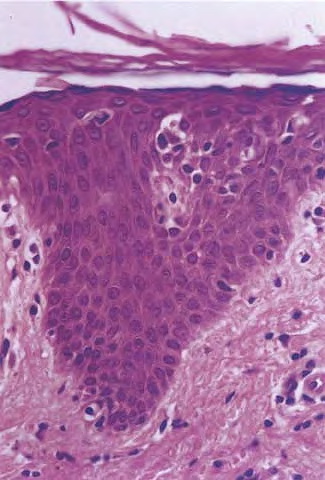

Mycosis Fongoïde =التفطر الكمئي